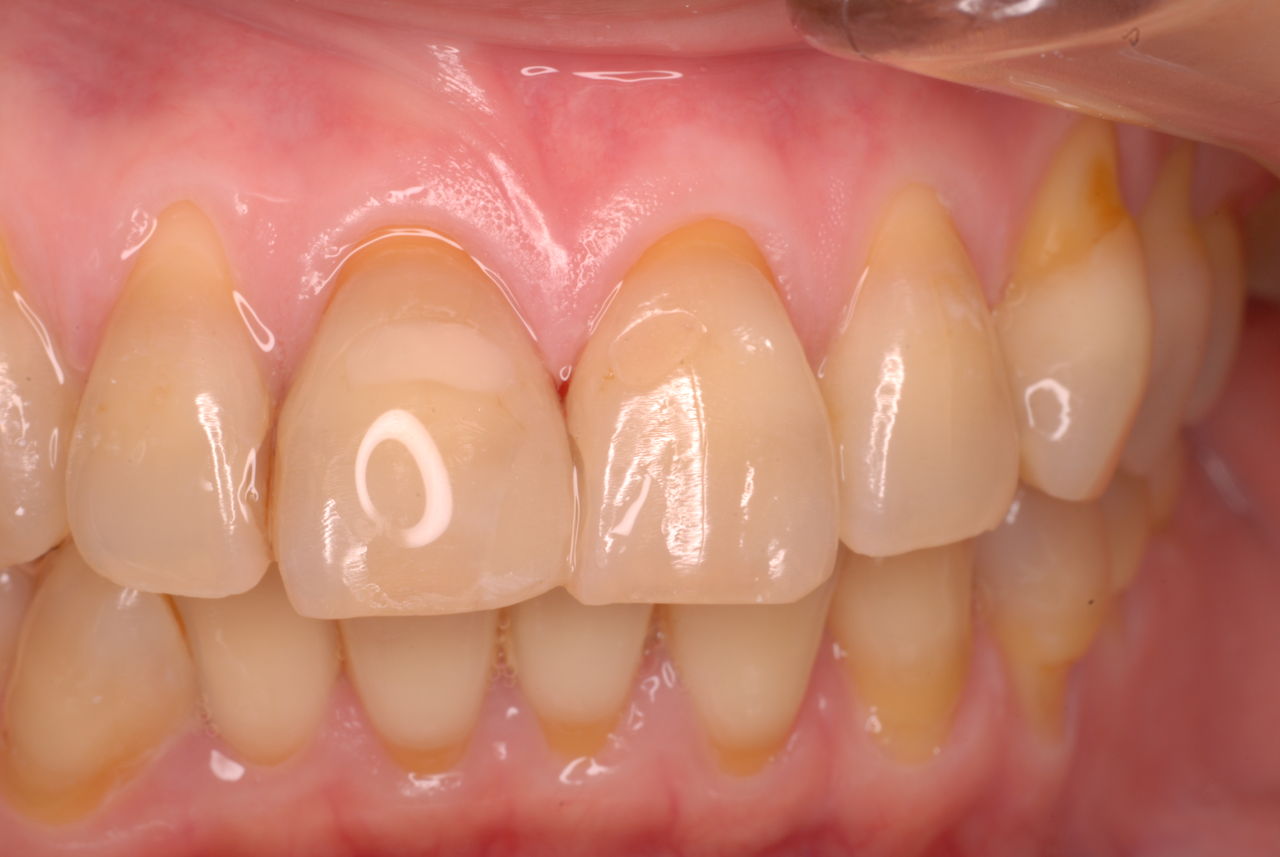

歯周病になっていましたが、少し色が黄色くなっているだけで比較的綺麗な歯の状態です。

平成9年来院神経を取り、同時に歯周病の話をしてそのまま来なくなっていたかたですが、たまたま一部欠けてきました。それで来院。